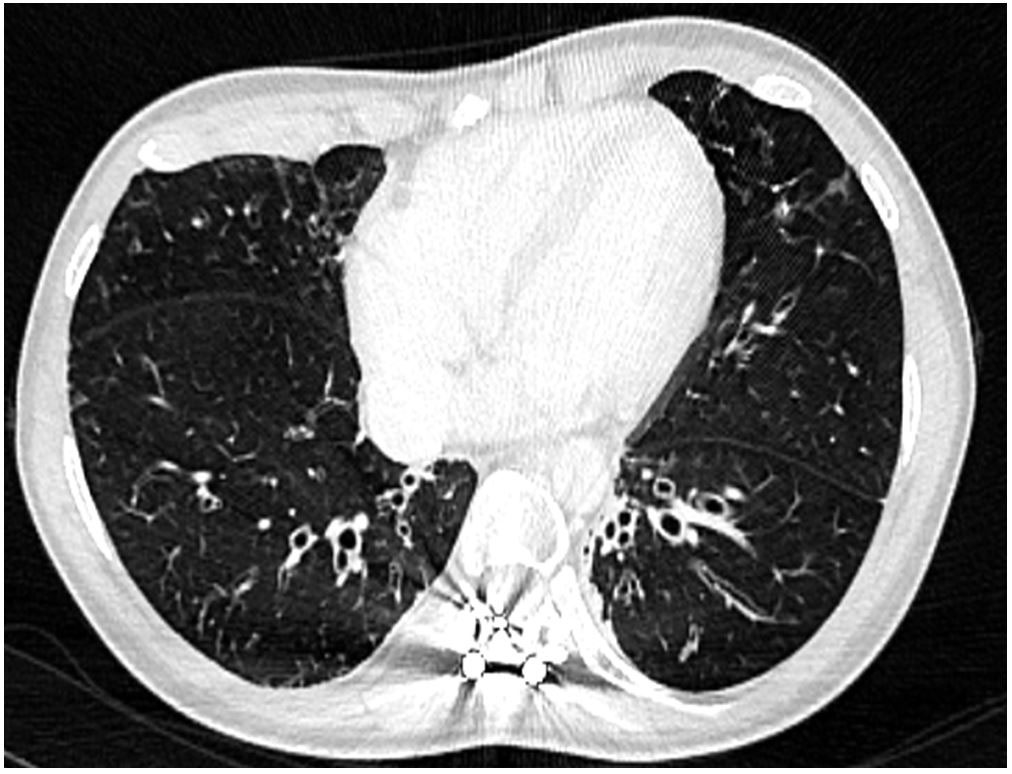

A 27-year-old female was referred to our department for management of an autoimmune haemolytic anaemia. Recent medical history included a diffuse large B-cell lymphoma at the age of 20 with negative Epstein-Barr virus (EBV) serology. She was considered in remission after four courses of rituximab, adriamycin, cyclophosphamide, vincristine, bleomycin, prednisone and intrathecal methotrexate, and consolidation with 2 infusions of methotrexate followed by successful autologous stem cell transplantation. During and after chemotherapy she had many bacterial infections and two episodes of herpes zoster reactivation. Examination of her childhood medical history found neonatal dwarfism and scoliosis with spinal osteosynthesis (fig. 1A), recurrent acute pulmonary and ear, nose and throat (ENT) infections with otitis media from the ages of 3 to 10 years, requiring placement of tympanostomy tubes at the age of 6 and adenoidectomy. The patient described frequent bronchitis and sinusitis requiring antibiotic courses two or three times a year, complicated by bronchiectasis (fig. 1B).

Figure 2 Thoracic computed tomography confirming the X-ray findings.